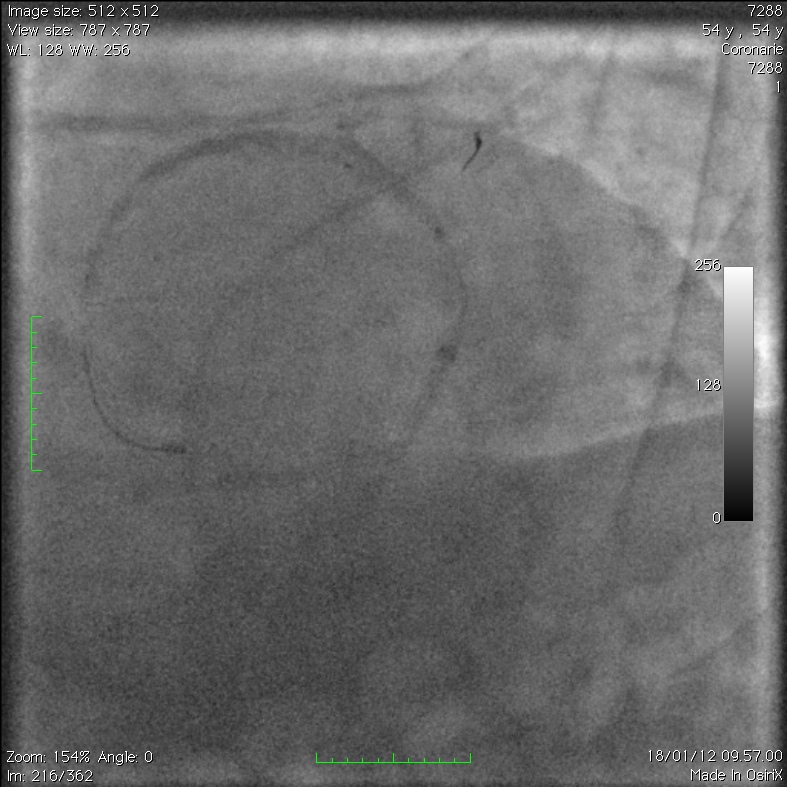

Extensive Intramural Coronary Hematoma Following Balloon Catheter

Extensive Intramural Coronary Hematoma Following Balloon Catheter Catheter Balloon Rupture Silicone catheters burst at lower. We report 6 cases that highlight the potential consequences of. foley balloon rupture can lead to a urinary tract infection and/or sepsis requiring antibiotic therapy. the primary reason for the catheter balloon not deflating is malfunction of the inflation valve caused by external clamping, crushing or. these cases demonstrate circumstances of foley. Catheter Balloon Rupture.

Extensive Intramural Coronary Hematoma Following Balloon Catheter Catheter Balloon Rupture balloon rupture is an infrequent complication of cardiac catheterization that can lead to vessel injury. these cases demonstrate circumstances of foley catheter balloon rupture that result from overinflation during. To assess the volume of foley catheter balloon rupture and the incidence of free fragment formation. predictive factors for balloon rupture may help identify patients who are at. Catheter Balloon Rupture.

Extensive Intramural Coronary Hematoma Following Balloon Catheter Catheter Balloon Rupture latex catheter balloons tolerate higher fill volumes but have a high likelihood of releasing fragments. the primary reason for the catheter balloon not deflating is malfunction of the inflation valve caused by external clamping, crushing or. we aimed to assess the volume of foley catheter balloon rupture and incidence of free fragment formation and to provide guidance. Catheter Balloon Rupture.

Extensive Intramural Coronary Hematoma Following Balloon Catheter Catheter Balloon Rupture latex catheter balloons tolerate higher fill volumes but have a high likelihood of releasing fragments. we aimed to assess the volume of foley catheter balloon rupture and incidence of free fragment formation and to provide guidance through clinical scenarios on the management of overinflation. these cases demonstrate circumstances of foley catheter balloon rupture that result from overinflation. Catheter Balloon Rupture.